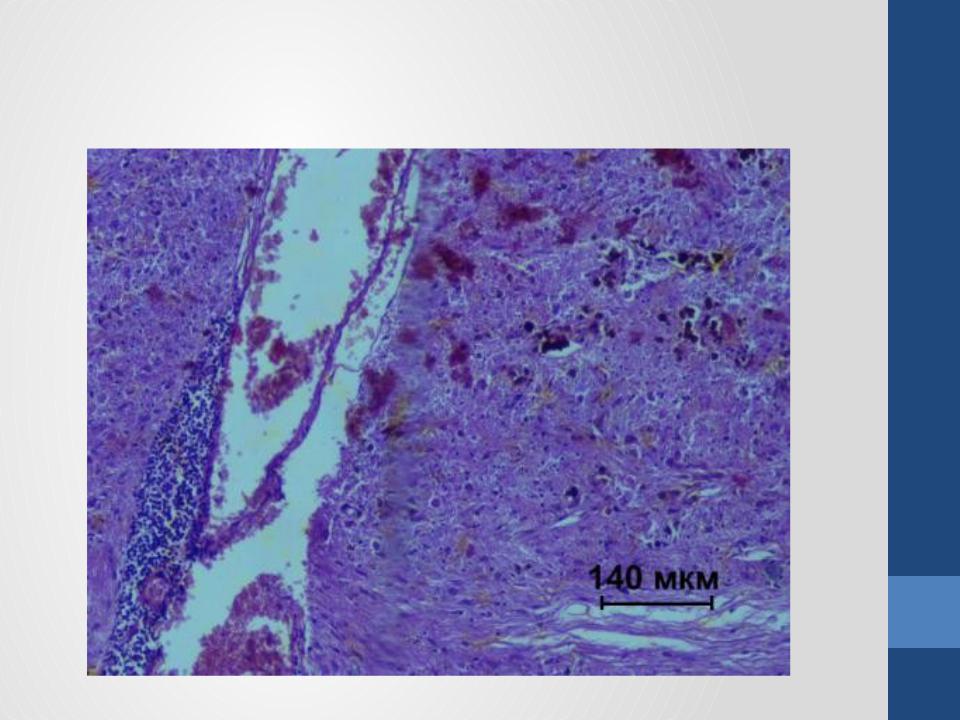

- •Гистологическая картина гемангиомы

- ••Клеточная гемангиома - наиболее незрелая и примитивную по своему гистологическому строению форма этой

- •Капиллярная гемангиома развивается в первые дни или недели жизни.

- •Кавернозная гемангиома состоит преимущественно из зрелых сосудов и синусоидальных кровяных областей.

- •Комбинированная (капиллярно-кавернозная) гемангиома